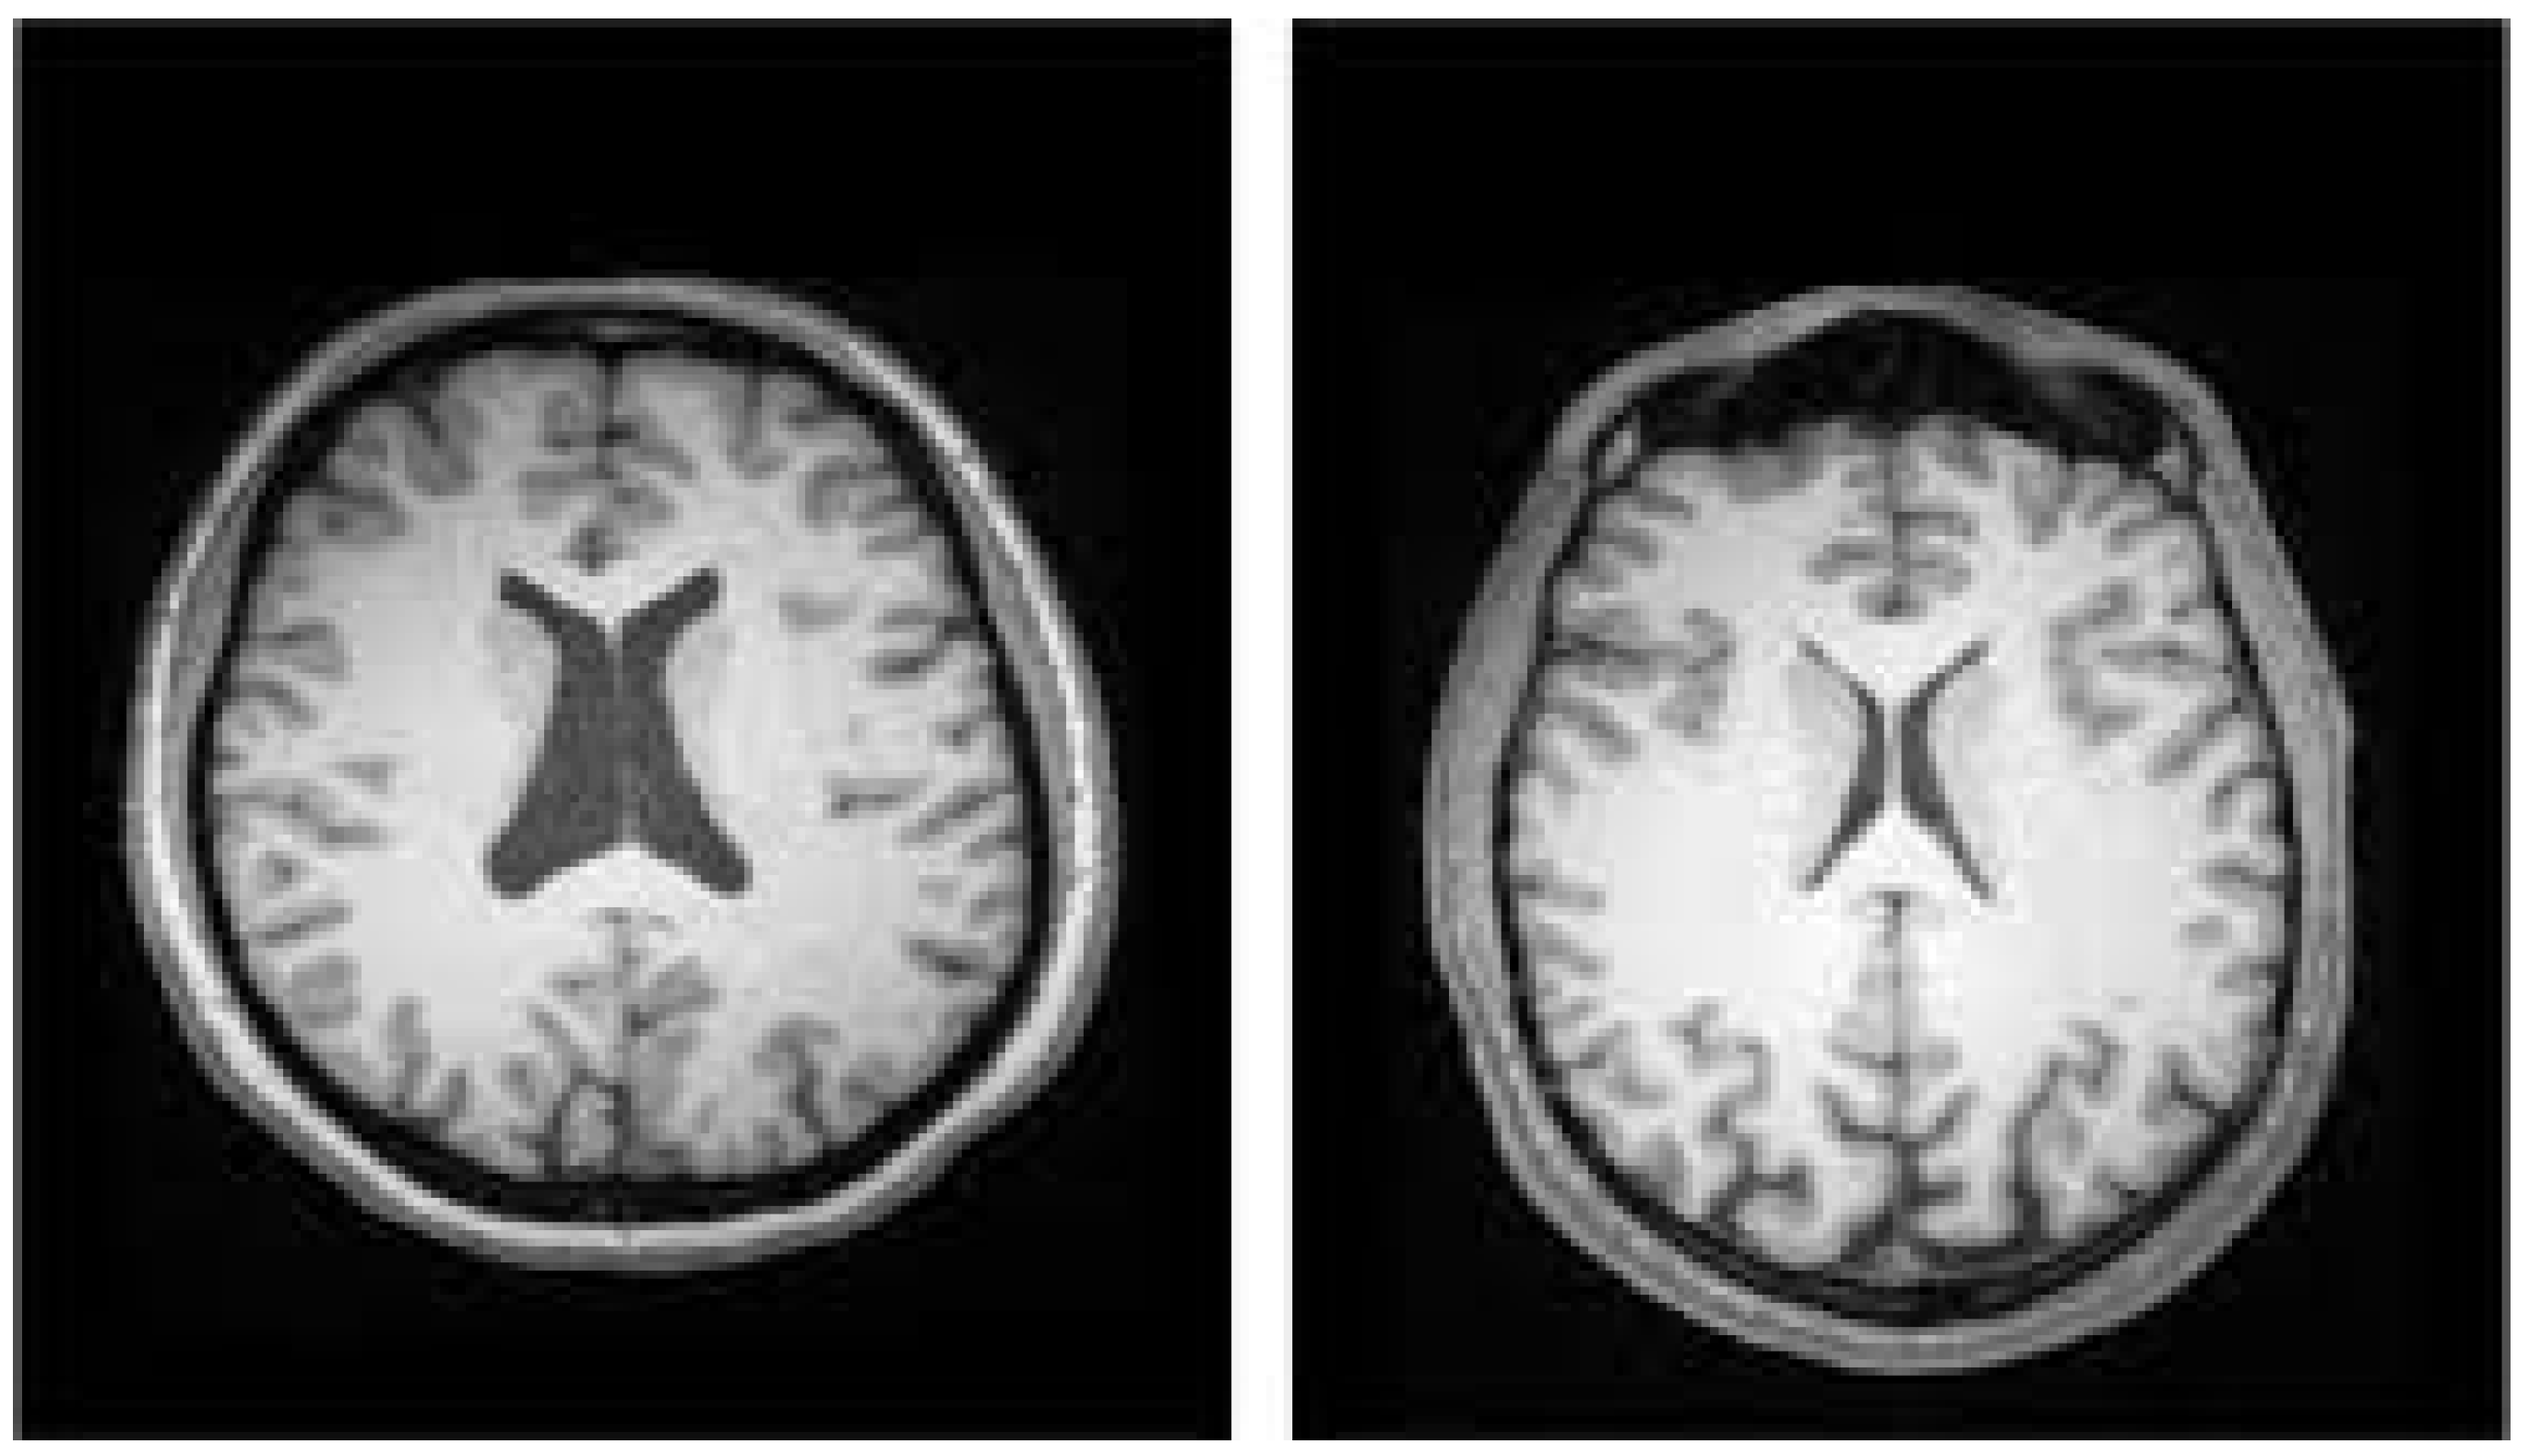

- SZ is linked to modest structural abnormalities in the brain, such as variations in gray-matter volume and cortical thickness. These modifications might vary greatly between individuals, making it difficult to create models that accurately capture these differences. More complex models can be built using advanced ML techniques and larger datasets.

- Gaser, C.; Nenadic, I.; Buchsbaum, B.R.; Hazlett, E.A.; Buchsbaum, M.S. Ventricular enlargement in schizophrenia related to volume reduction of the thalamus, striatum, and superior temporal cortex. Am. J. Psychiatry 2004, 161, 154–156. [Google Scholar] [CrossRef] [PubMed]